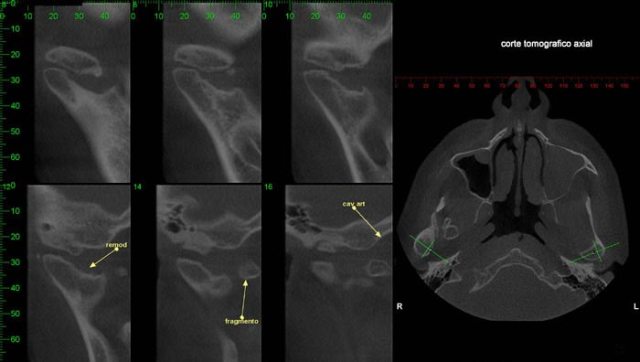

CASO 3 - Fratura de ATM

Paciente com história clínica de trauma. Fratura no côndilo direito com deslocamento do fragmento para medial e deslogamento do côndilo para lateral da cavidade articular.